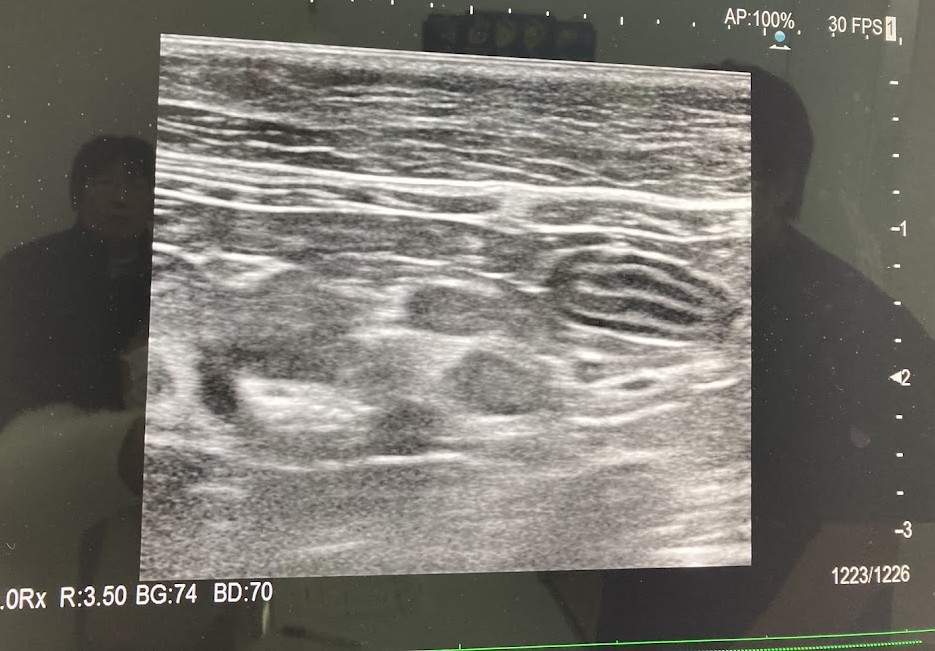

それよりも獣医さんが気にしていたのは、エコー検査。

「小腸は通常五層になってるのですが、途中で断絶している。つまりリンパ節が腫れている様子」

「肝臓に白い点々がたくさんあるようで、結節やガンかもしれない」

・エコー検査をしたら小腸の五層構造が乱れていた